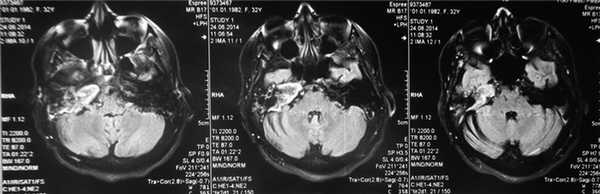

На КТ правой височной кости определяется затемнение в области аттика и антрума, цепь слуховых косточек сохранена (рис. 3, а). Рисунок 3. КТ и МРТ височных костей больного А. с адгезивным средним отитом справа, фиброзной облитерацией аттика. а — КТ; б — МРТ основания черепа в режиме Т1; в — в режиме Т2; г — в режиме non-EPI DWI.

Пациенту выполнена МРТ основания черепа по описанной методике (рис. 3, б—г).

В режиме Т1 и Т2 справа определяется очаг с высокой интенсивностью сигнала, тогда как в режиме non-EPI DWI патологических образований не выявлено. Диагноз: адгезивный средний отит справа, фиброзная облитерация аттика.

В связи с отсутствием данных о холестеатоме операция не производилась, выявленные изменения расценены как фиброзные изменения, оторея была обусловлена периодическим возникновением наружного отита. Больной получал консервативное лечение.